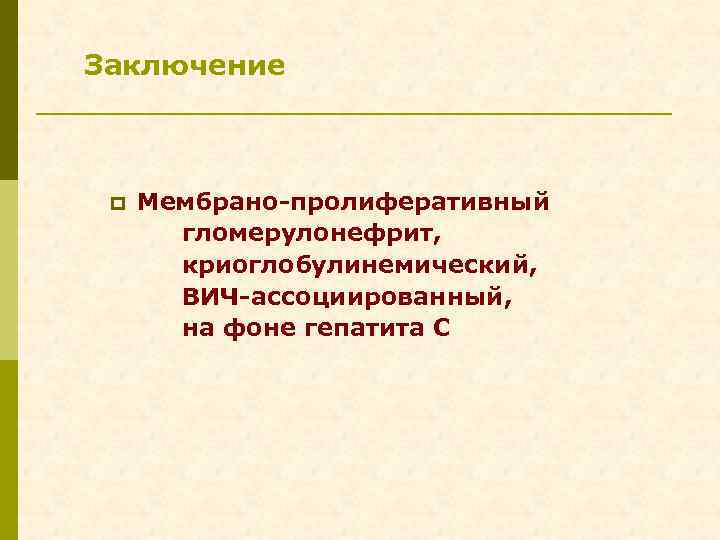

Заключение p Мембрано-пролиферативный гломерулонефрит, криоглобулинемический, ВИЧ-ассоциированный, на фоне гепатита С

4 случая ВИЧ – 4 варианта морфологических феноменов ВИЧ-ассоциированной нефропатии p А – ФСГС, tip lesion p Б – МПГН криоглобулинемический p В – мембранозная нефропатия + ФСГС коллаптоподобный p Г – Ig. A нефропатия